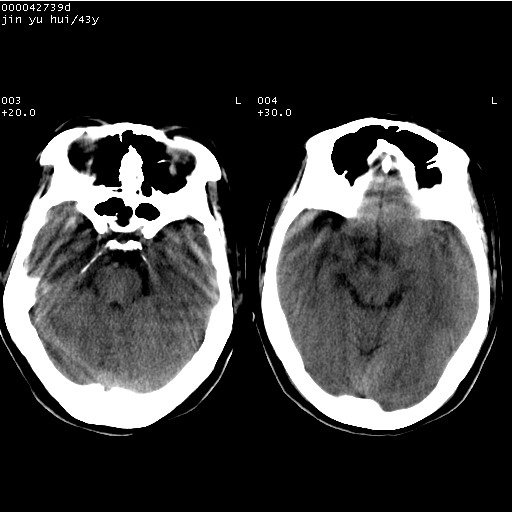

患者 女,43岁。头部外伤26天,经住院治疗,现头痛减轻。申请ct复查,了解颅内情况。

临床诊断:2级脑外伤。

颅脑ct轴位平扫(层厚、层距均为10mm),图像如下:

伴硬膜下水瘤

硬膜下水瘤

大脑镰左旁硬膜下血肿慢性期。

大脑镰左旁慢性硬膜下血肿.

左大脑镰旁硬膜下慢性血肿。

是不是应该为:大脑镰左旁硬膜下血肿吸收期更妥当些;

大脑镰左旁硬膜下积液